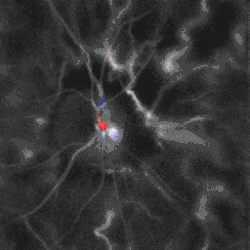

Blood flow in the retina and choroid in the optic disc region can be revealed non invasively by near-infrared laser Doppler imaging.[4] Laser Doppler imaging can enable mapping of the local arterial resistivity index, and the possibility to perform unambiguous identification of retinal arteries and veins on the basis of their systole-diastole variations, and reveal ocular hemodynamics in human eyes.[5] Furthermore, the Doppler spectrum asymmetry reveals the local direction of blood flow with respect to the optical axis. This directional information is overlaid on standard grayscale blood flow images to depict flow in the central artery and vein.[6]